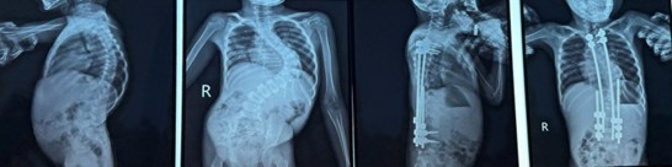

Despite these challenges, two operating tables ran side-by-side each day, with two surgeons per table. The cases ranged from adolescent idiopathic scoliosis and posterior cervical fusion up to the occiput, to growing rods, extension of prior fusions, and highly complex congenital and neuromuscular scoliosis.

The learning opportunities were immense, but the impact on patients’ lives was even greater. One of the most sobering moments came as we prepared for our 14th case - a young patient with one of the most severe spinal curves we had seen. Tragically, shortly after induction, she developed malignant hyperthermia - a rare and life-threatening anaesthetic emergency. Thanks to the swift action of our NZ anaesthetists, her life was saved. While we were relieved, there was a strong sense of unfinished business, as this surgery had represented her one opportunity for treatment.

Among the many children we met, Ratha’s story stands out. At just four years old, he struggled to breathe and couldn’t walk until nearly three due to a congenitally deformed spine. His parents discovered the Children’s Surgical Centre through social media and sought help. Our voluntary spine team brought expertise and compassion to provide care that was otherwise unavailable in Cambodia.

Children like Ratha, suffering from severe scoliosis, congenital deformities, or spinal injuries, received not only surgical treatment but also renewed hope. The team’s visit also strengthened local capacity through training and knowledge sharing with Cambodian surgeons and nurses.